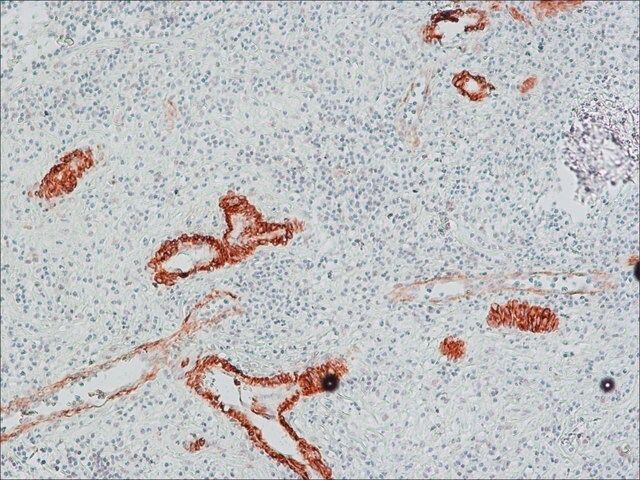

| technique(s) | immunohistochemistry: suitable indirect ELISA: suitable western blot: suitable |